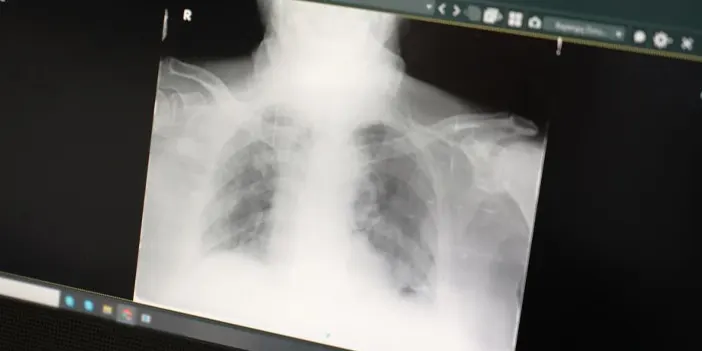

Samsun’dan tepki geldi! “Yoğun bakımlar amacından fazla hizmet veriyor”

Göğüs Hastalıkları Uzmanı Prof. Dr. Şevket Özkaya, yoğun bakım ünitelerinin amacının dışına çıkıp, kritik hastalar yerine bakım desteği ihtiyacı olan yaşlılara hizmet etmeye başladığını belirtti. Prof. Dr. Özkaya, yoğun bakım yataklarının organ yetmezliği ve hayati tehlikesi olan hastalar yerine, yakınları olmayan veya bakılmak istenmeyen yaşlılar ve bakım hastalarıyla dolu olduğunu ifade etti.